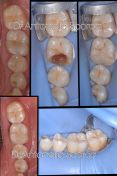

Intarsio in composito per la sostituzione di vecchia otturazione infiltrata (carie al di sotto della vecchia otturazione). In 2 sedute è possibile restaurare in maniera definitiva uno o più denti mediate tecniche moderne di ricostruzione dei denti con intarsi in composito cementati con diga di gomma.